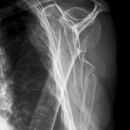

Fraktur Coracoid und Ala scapulae